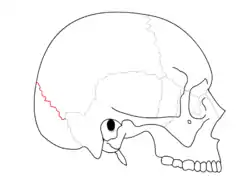

The lambdoid suture (or lambdoidal suture) is a dense, fibrous connective tissue joint on the posterior aspect of the skull that connects the parietal bones with the occipital bone. It is continuous with the occipitomastoid suture.

The lambdoid suture is between the paired parietal bones and the occipital bone of the skull. It runs from the asterion on each side.

The lambdoid suture is named due to its uppercase lambda-like shape.

Animation. Lambdoid suture shown in red.